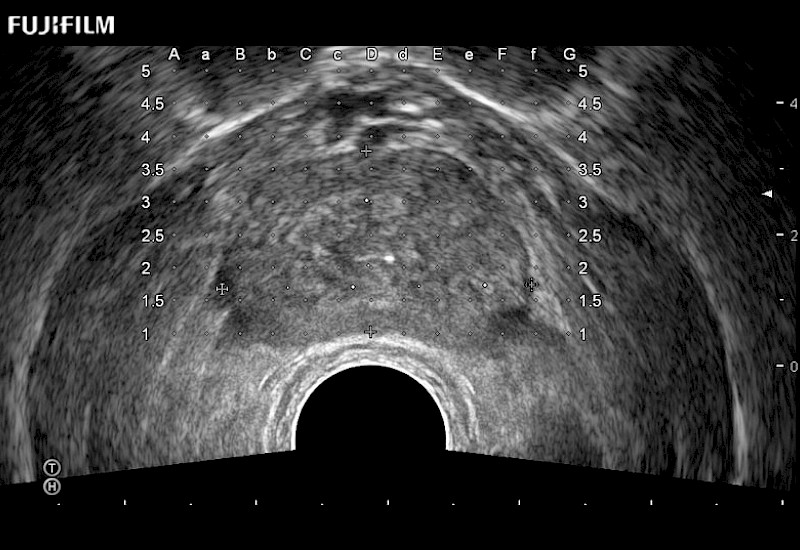

Exclusive 200° FOV end-fire prostate biopsy transducer.

Main Specifications:

Provides real-time imaging of both the sagittal and transverse planes